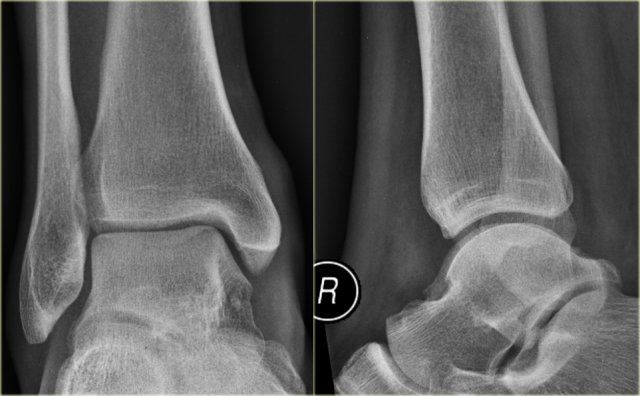

Example 2

• First impression

There is a fracture of the posterior malleolus.

Classification according to Weber is not possible.

An isolated fracture of the posterior malleolus is uncommon, but as part of a supination exorotation (Weber B) or pronation exorotation injury (Weber C) it is quite common.

So we have to re-examine the films to look for signs of a Weber B or C fracture.

• Re-examination

No sign of an oblique fracture of the lateral malleolus, so we can exclude a Weber B fracture.

There is still the possibility of a Weber C fracture, i.e. medial rupture or avulsion, high fibular fracture and finally a posterior malleolar fracture.

Now we notice the subtle avulsion of the medial malleolus (red arrow).

Additional radiographs of the lower extremity demonstrate a high fibular fracture (blue arrow).

• Final report

Weber C stage 4.